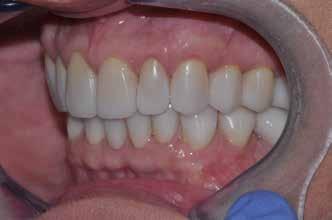

A tényleges protetikai ellátás megkezdése előtt a páciens mosolygás közben látható fogait otthoni fogfehérítés keretei között a kérésének megfelelő A1-es fogszín eléréséig fehérítettük. A fehérítés során a későbbiekben héjakkal ellátásra kerülő fogak színén nem változtattunk. A fogak előkészítése részeként csupán a két felső nagymetsző (1.1,2.1) incizális élét kellett kismértékben redukálni. A többi felső front fog (1.3,1.2,2.2,2.3) nem került preparálásra.

A héjak átadását követően kialakuló állapot valósághű módon történő bemutatása érdekében próbapasztát alkalmaztunk (Try-In-Paste; Variolink® Esthetik Try-In-Paste, Ivoclar Vivadent) (11. ábra). A próba során ellenőrizzük a héjak színét, formáját és transzparenciáját. A próbapaszta alkalmazásának egyik lényeges pontja, hogy a paszta színe egyezzen meg a végleges beragasztás során alkalmazni kíván ragasztóanyag színével. A héjak végleges rögzítése során mindig adhezív rendszereket használunk.

nak megfelelően – előkészítjük (orthofoszforsavval történő savazás, lemosás, szárítás és bond réteggel történő fedés). Ezzel egyidejűleg a ragasztásra kerülő héjak is előkészítésre kerülnek (hidrofolysavval történő savazás, lemosás, szárítás, szilanizálás, bond réteggel történő fedés, és végül az alkalmazni kívánt ragasztóanyag felvitele). Ezután a héjakat a fogak felszínén egyesével pozicionáljuk, majd néhány másodpercen keresztül polimerizációs lámpa segítségével megvilágítjuk. Ezt követően a kifolyó ragasztófelesleget eltávolítjuk, majd elvégezzük a restaurátumok végső polimerizálását. A héjak végleges rögzítését követően az esetlegesen visszamaradt ragasztómaradványok eltávolításra kerülnek, valamint ellenőrizzük az okklúzió és artikuláció közben létrejövő fogérintkezéseket. Az optimális esztétikai eredmény biztosítása érdekében kiemelt jelentősége van a papillák helyreállításának (rózsaszín esztétika). A modern fogorvoslás egyik kiemelt célja a fehér- és rózsaszín esztétika közti harmonikus egyensúly megteremtése. A papillák színe, nagysága és szimmetrikus megjelenése meghatározó szerepet tölt be a rózsaszín esztétika kialakításában. Az íny lefutása ugyancsak rendkívül jelentős mértékben befolyásolja a páciens fogazatának esztétikus megjelenését.